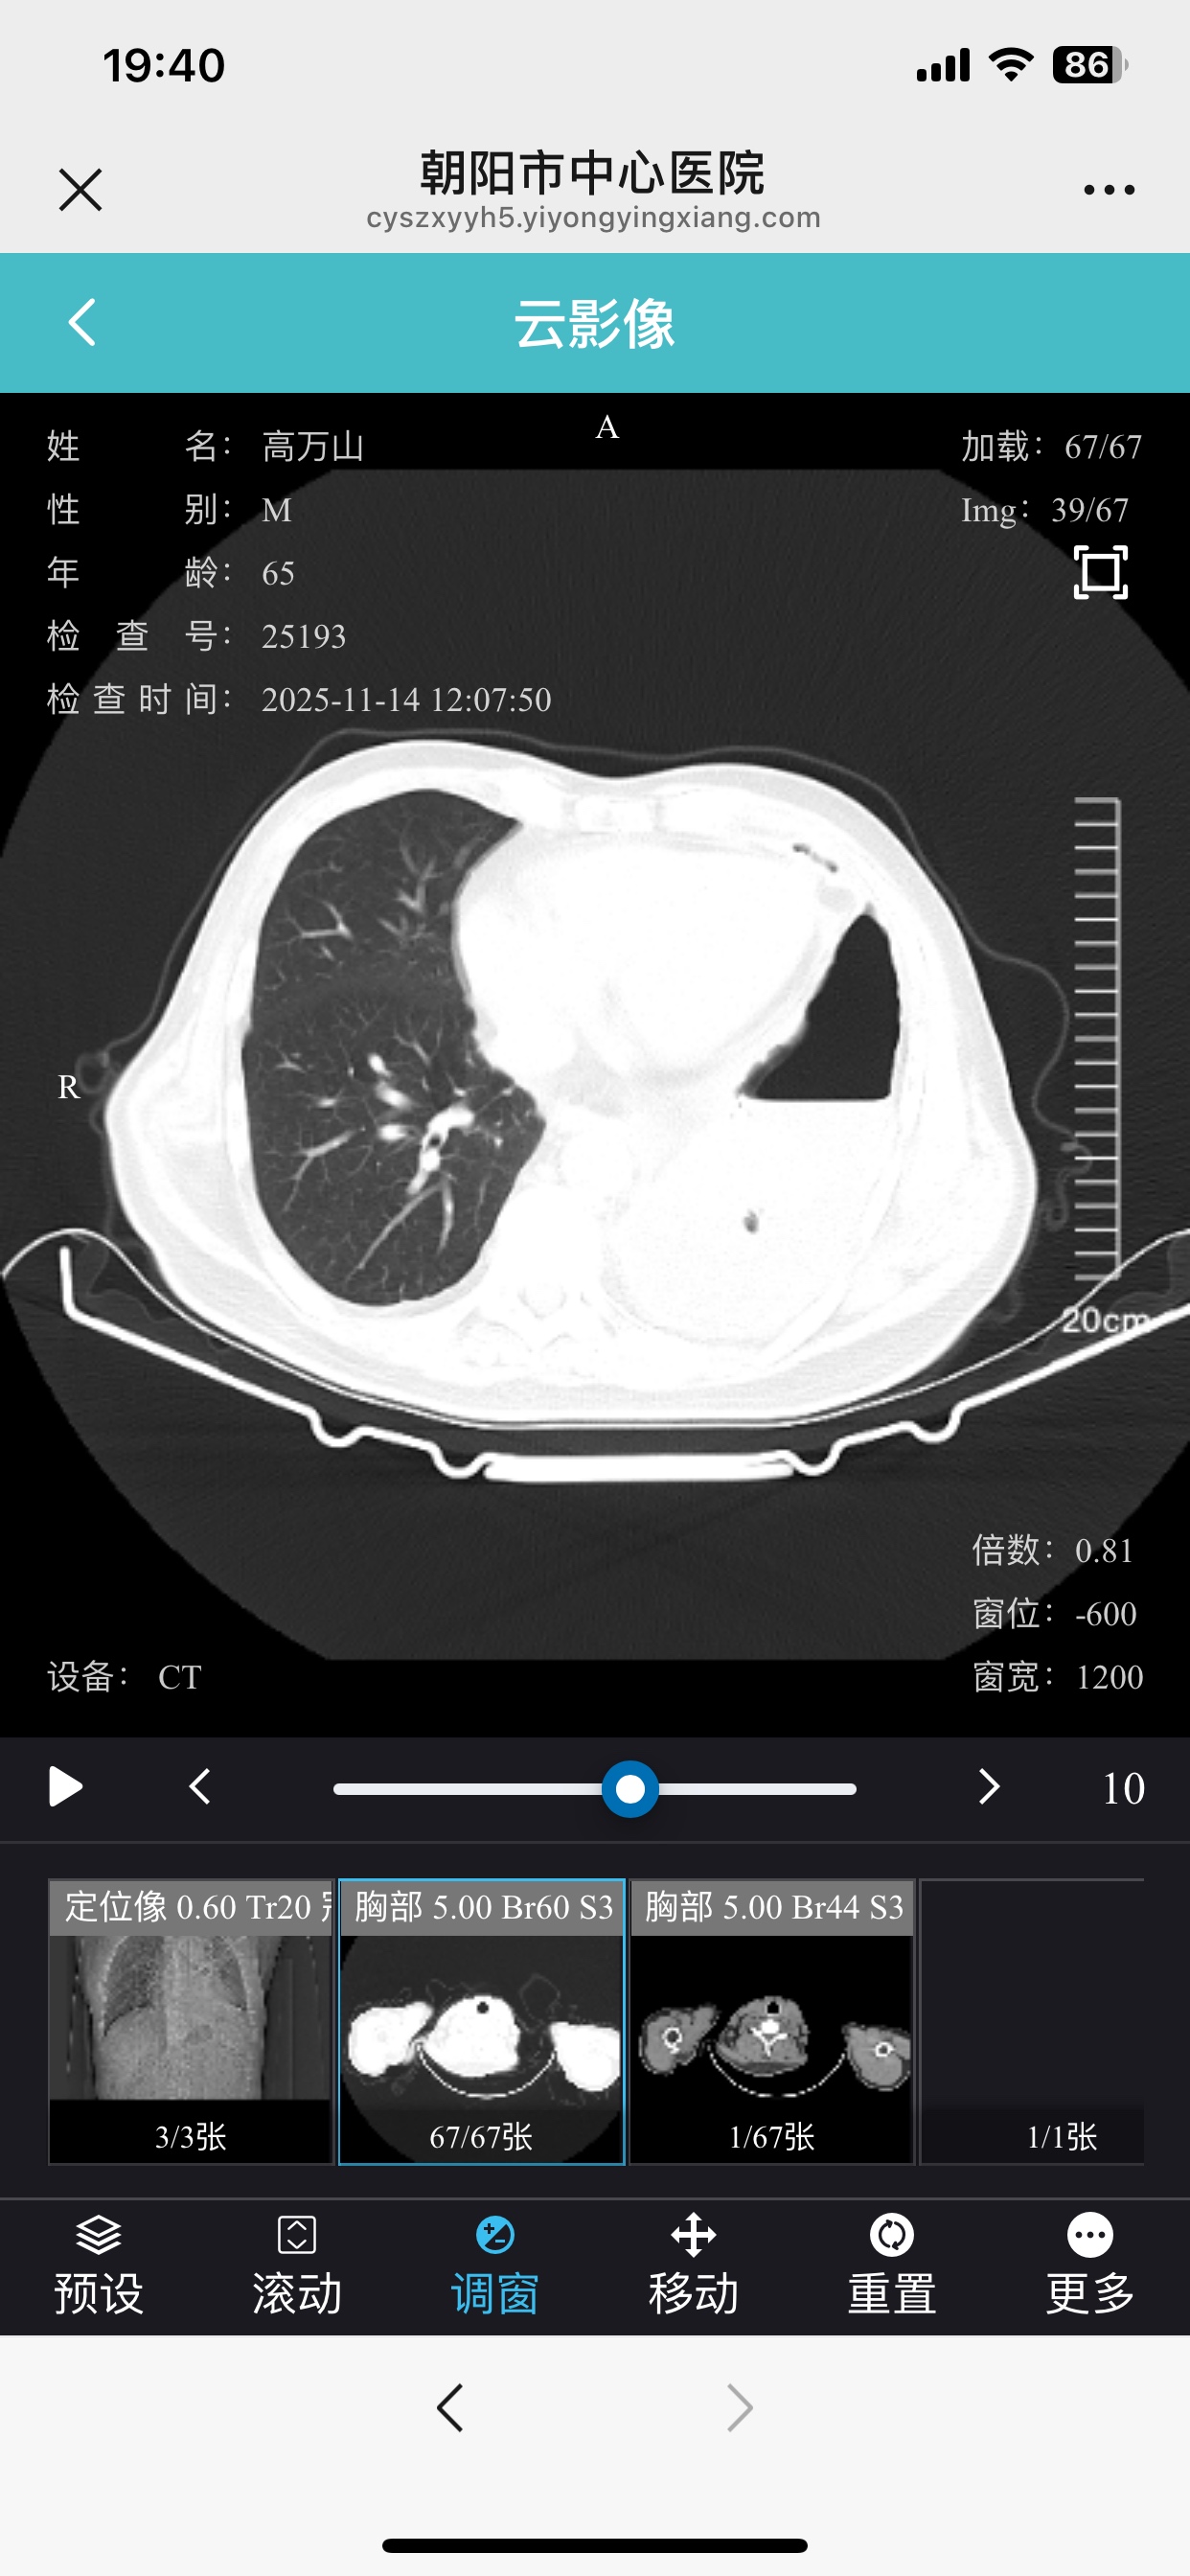

服用吉非替尼21天后复查 癌胚抗原从197升到376 是不是吉非替尼无效啊

登录/注册后可看大图

体感也不太好 拍了ct胸水还是涨起来了

影像为准,如果确实效果不好,换三代再试试

治疗过程尽量详细点,不明确靶点,没有影像复查对比,没办法说效果,还有一个问题,吉非替尼无效,二三代有效率并不高的

拍Ct 肿瘤有变化吗

刚开始吃如果有效肿瘤会缩小